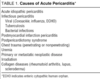

What is the typical history of pericarditis?

- Secondary to viral illness (recent cough)

- Retrosternal sharp chest pain localised to front of chest

- Aggravated with inspiration, cough, lying flat

- Eased by sitting up and leaning forward

- May hear pericardial rub